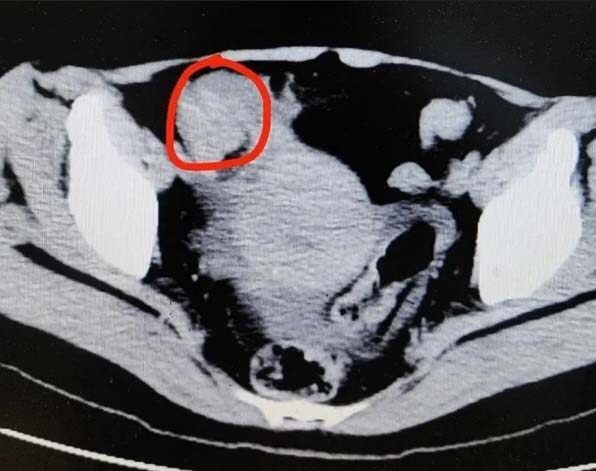

펑씨는 가로 4cm, 세로 3cm 크기의 결석이 소장을 막아 음식물이 정상적으로 통과하지 못하는 상태였다. 항저우 제 1인민병원 의료진은 펑씨의 소장을 일부 절제했으며 결석 생성 원인으로 펑씨가 섭취한 음식을 꼽았다.

펑씨의 소장에는 가로 4cm, 세로 3cm 크기의 결석이 생긴 상태였다./사진=항저우일보